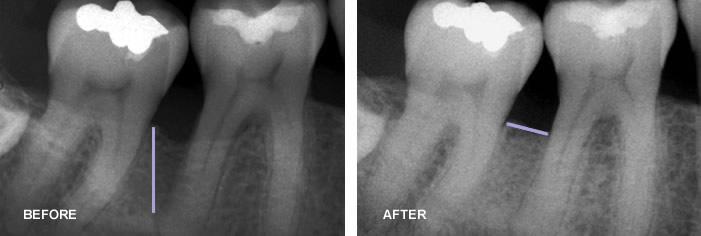

Periodontal regeneration I

Periodontal Bone Regeneration